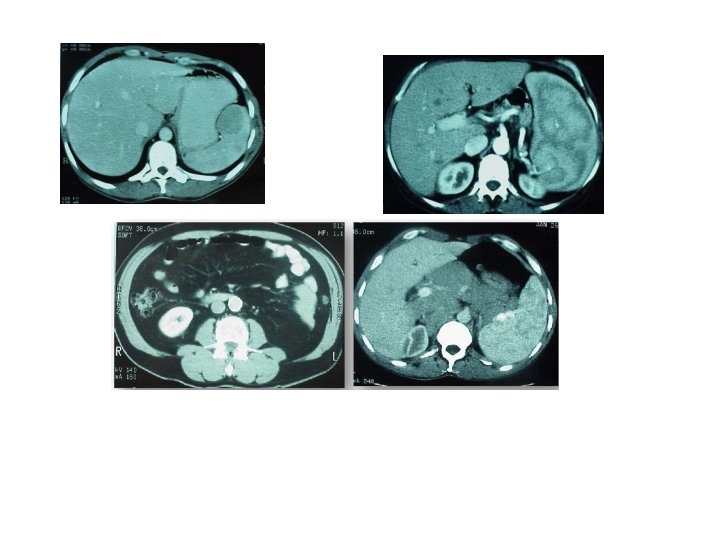

Bilan initial Pet scan: stade IV Hépatique FDG initial D. Bordessoule 2013